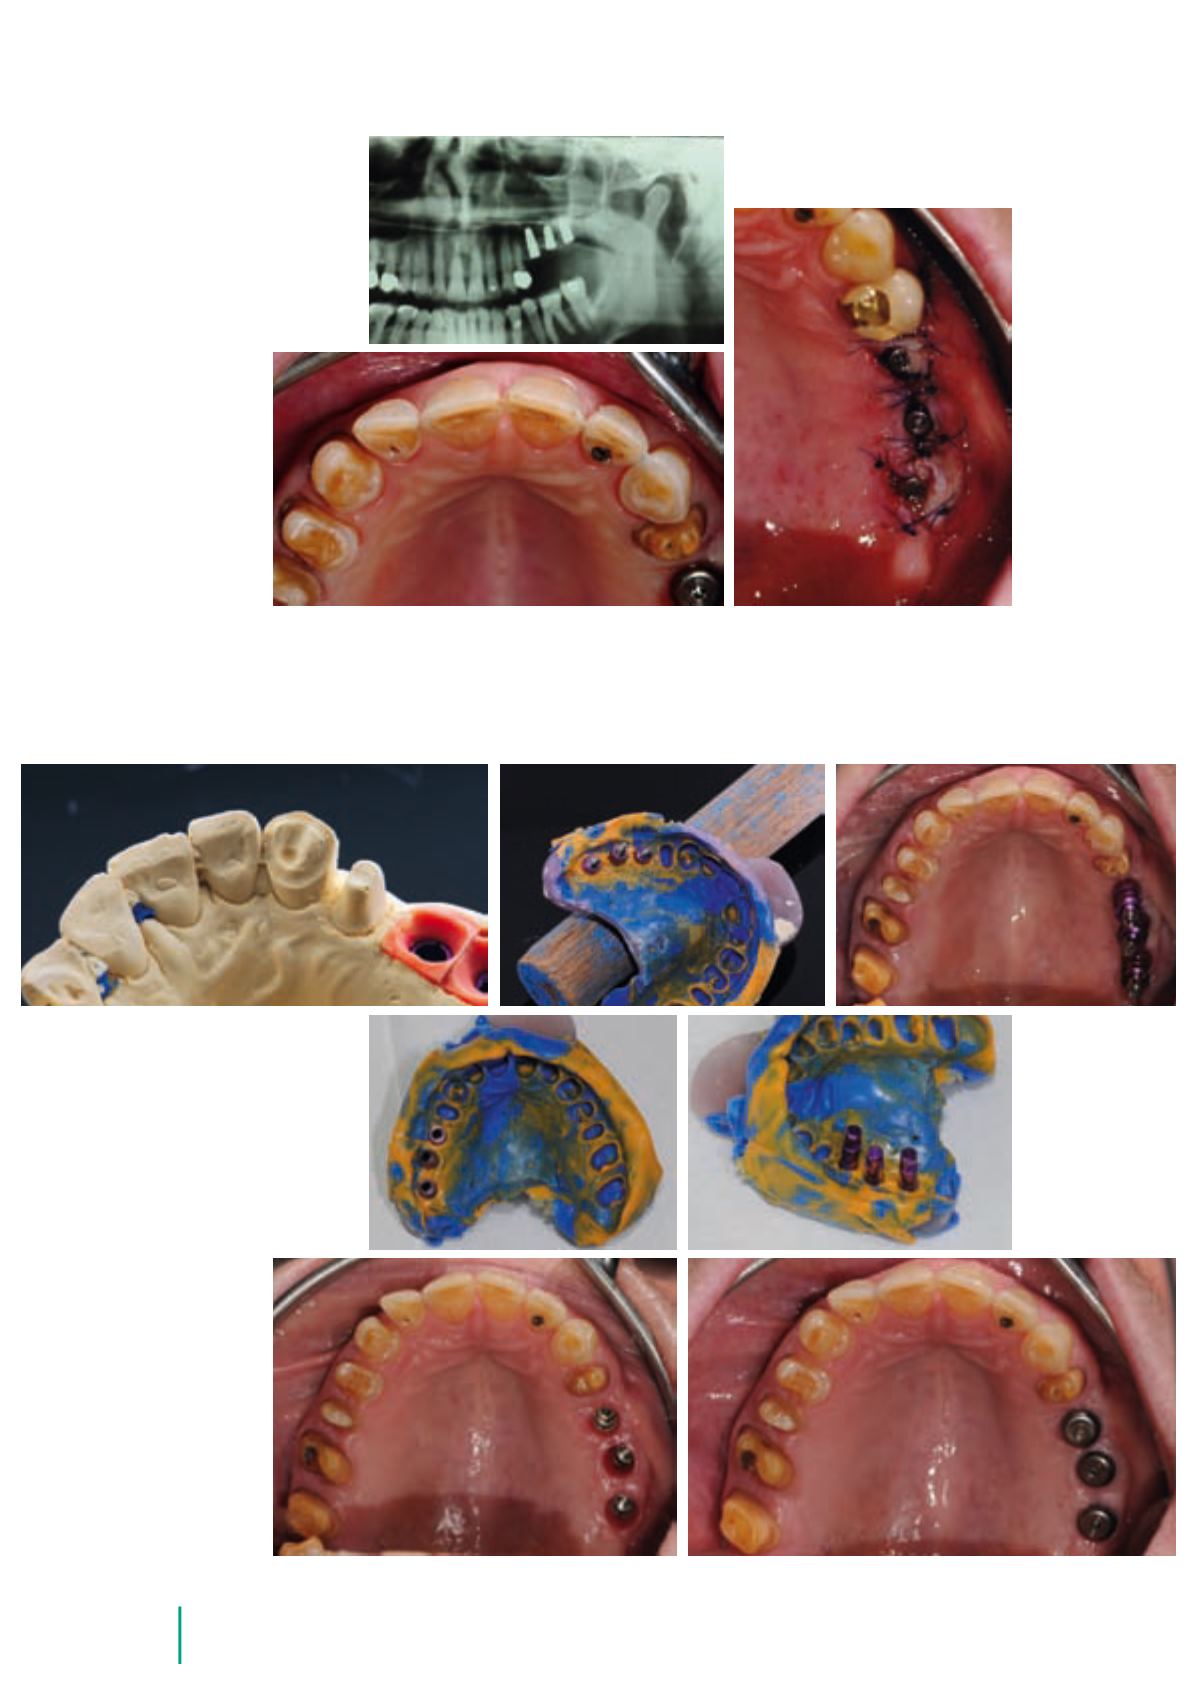

Abb. 26

Orthopantomographie

(OPG) nach Implantation

Abb. 30 bis 35

Abformung und

Einschrauben der

Laboranaloge

Abb. 27

Präzise

Schnittführung

über den

Implantaten

Abb. 28

und 29 Inzisal-

palatinales

Veneer auf 23